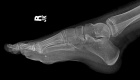

Patient is a 15 y/o male who presented c/o 9 month hx. of R. plantar foot pain w/ ambulation and palpable mass

Physical exam: there is a palpable 7x3 cm mass over the med-plantar aspect of R. foot; + tenderness to palpation; NVI

Zoom image: Radiological image Radiological image.